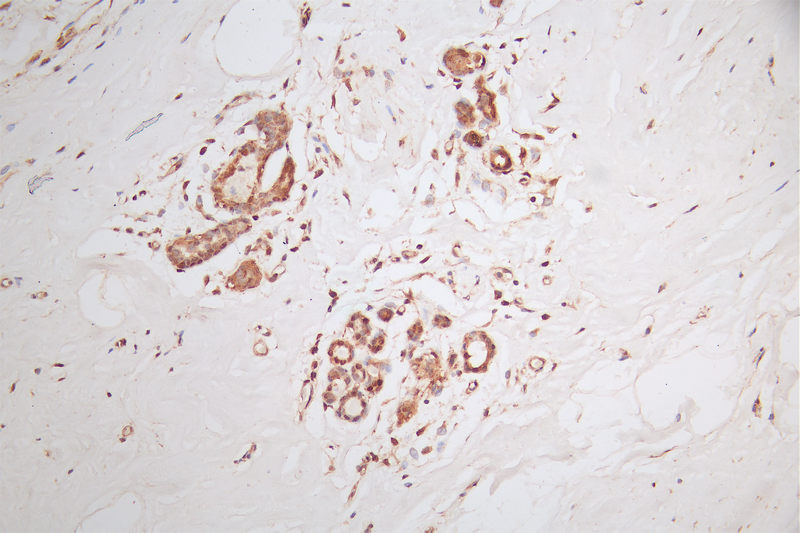

IHC image of CSB-RA150369A0HU diluted at 1:50 and staining in paraffin-embedded human breast cancer performed on a Leica BondTM system. After dewaxing and hydration, antigen retrieval was mediated by high pressure in a citrate buffer (pH 6.0). Section was blocked with 10% normal goat serum 30min at RT. Then primary antibody (1% BSA) was incubated at 4°C overnight. The primary is detected by a Goat anti-rabbit polymer IgG labeled by HRP and visualized using 0.58% DAB.